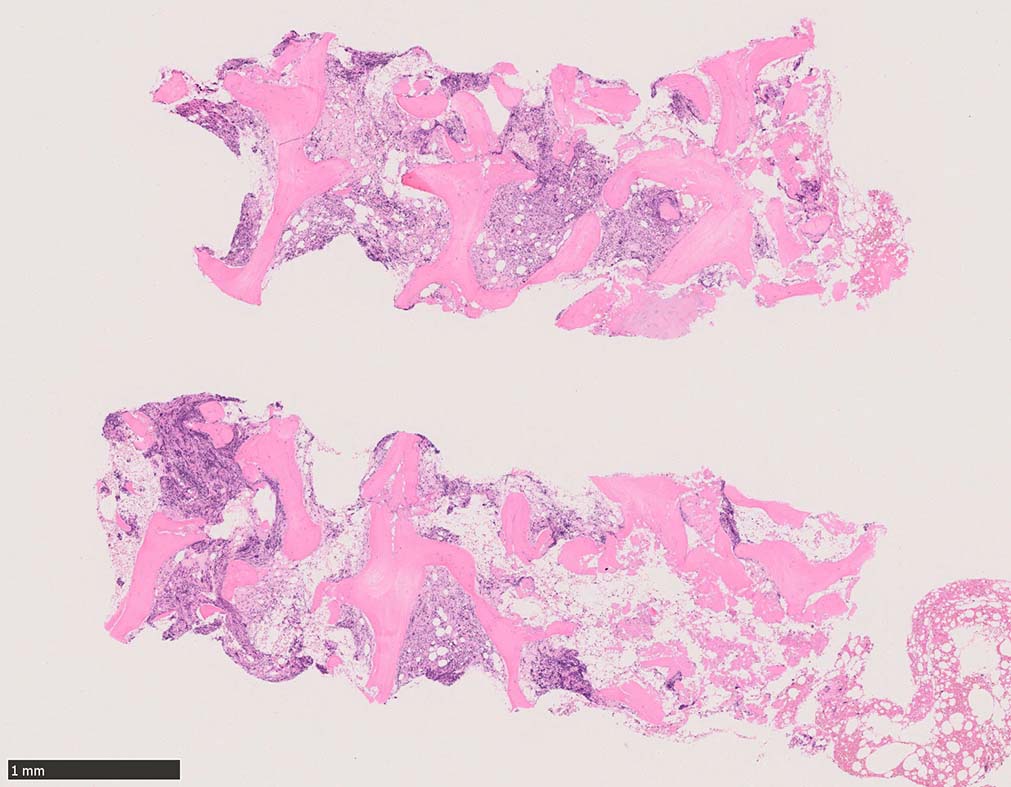

Case02; Meylofibrosis, overt fibrosis

77year-old female. 40歳時polycythemia veraと診断されていた.

[注] この症例は詳細は不明であるが, 過去にPVと診断されているため, PVに伴う二次性のmyelofibrosisの診断になる.

黒染する弾性線維の増生のほか, 赤く染まる膠原線維の増生が確認される. MF-2 fibrosis. 鍍銀染色の核染色をすると膠原線維の赤染がわからなくなるので行わない.